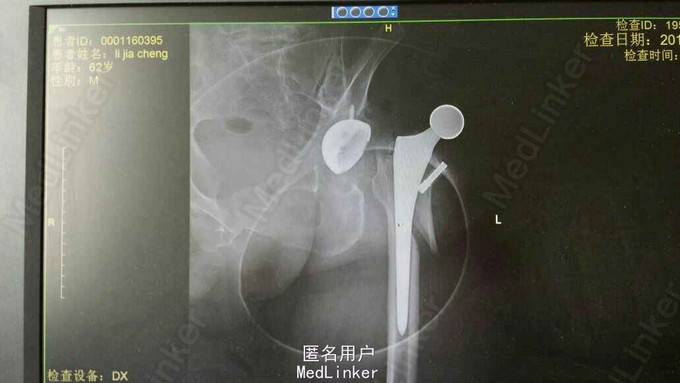

患者×××,男。60岁,“左侧人工全髋置换术后骨折”。于20天前因股骨头坏死行左侧人工股骨头置换手术治疗。术后20天翻身时出现脱位,在当地医院腰麻下行手法复位时出现骨折。故来院诊治。

左髋肿胀,压痛,左下肢呈短缩外旋畸形,较右下肢短缩约2cm。 x线检查:左髋脱位并左股骨干上端骨折。

左侧人工全髋置换术后髋关节脱位 左股骨干上段骨折 入院后完善术前检查,行切开复位内固定手术治疗。术中更换股骨头,用钢丝固定,术后皮牵引,3月后改为下肢支具固定。